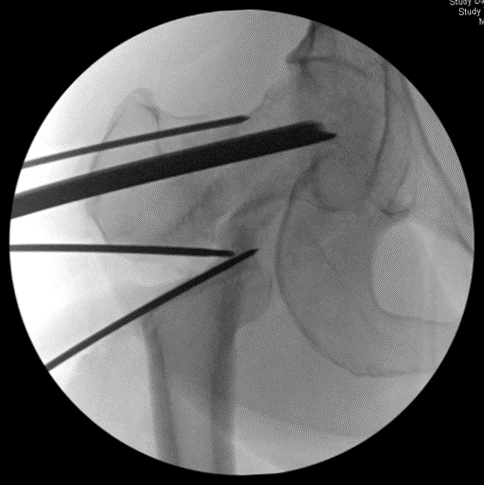

Intra-op fluoro imaging showing a 20 degree lateral closing wedge #osteotomy Both planning and performing the procedure take several hours. The procedure converts shear forces across the femoral neck nonunion into compressive forces, thus facilitating healing.

The wedge of bone has been removed, and the chisel for the blade plate has been inserted, both in accordance with the pre-op plan 📝

The plate is inserted. Notice the wire above the plate- this is to ensure no rotatory #malalignment is created after the #osteotomy